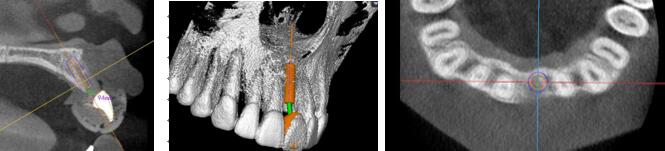

術(shù)前種植體規(guī)劃

術(shù)中實(shí)時(shí)導(dǎo)航

1.4mm球鉆定位△

2.3mm球鉆△

導(dǎo)航指示下2.2先鋒鉆擴(kuò)孔,導(dǎo)向桿檢查軸向及定位△

2.8mm擴(kuò)孔鉆△

26距25為3mm,26距27為4.71mm 26牙為4.10x11.50mm植體

術(shù)中實(shí)時(shí)種植導(dǎo)航

術(shù)后精度驗(yàn)證

種植體類 型植入點(diǎn) 末 端角 度

26 計(jì)劃<->實(shí)際 0.88 0.96 2.68